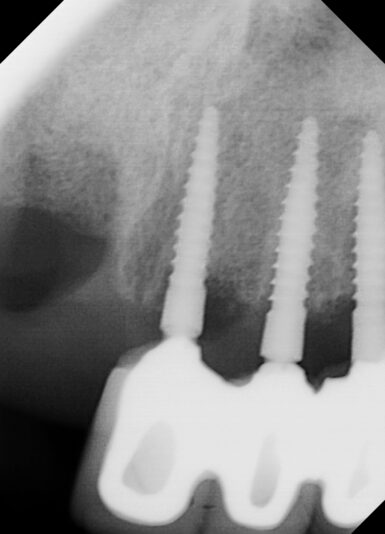

• I know this is an implant study club but I wanted to share a disappointment I had in my most recent bone graft. Patient came in for second opinion and after going over options and non restorable #31 I extracted and grafted the site. Post op PA showed that the M canal and defect was still present. This did have a buccal wall defect and I placed…

Read more